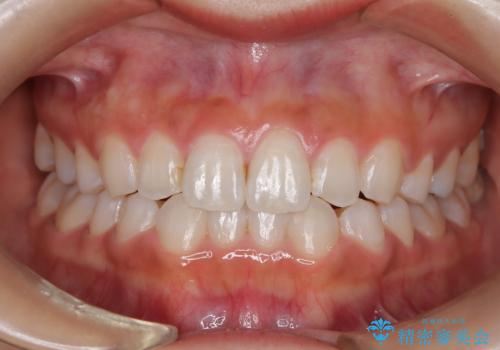

- 子供のころに矯正治療をされていたが、後戻りをしてしまったという20代女性の患者様です。上顎左右の2番が、咬合時に下顎の歯よりも内側に入っているクロスバイトという状態でした。奥歯の咬合関係は変えずに、マウスピース矯正にて前歯の並びを綺麗なアーチに仕上げました。再度後戻りしてしまうリスクを軽減させるために、リテーナー(保定装置)をお渡ししています。